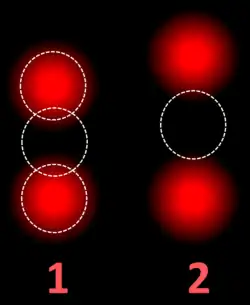

FISH can be used to measure the number of copies of the gene which are present and is thought to be more reliable than immunohistochemistry.[47] It usually uses chromosome enumeration probe 17 (CEP17) to count the amount of chromosomes. Hence, the HER2/CEP17 ratio reflects any amplification of HER2 as compared to the number of chromosomes. The signals of 20 cells are usually counted.

Two signals that are closer to each other than the signal diameter count as one. -